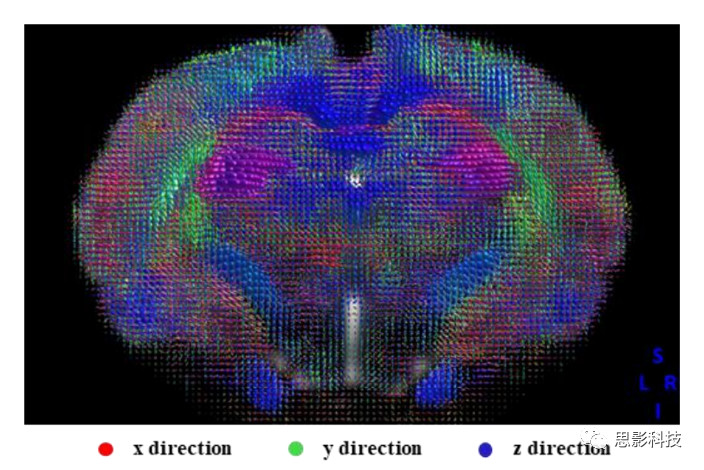

3、纖維追蹤

思影可根據(jù)不同的數(shù)據(jù)類型以及客戶的不同需求,可采取多種彌散模型(如彌散張量模型DTI、約束球形反卷積CSD、彌散譜成像DSI等等)

基于不同模型的確定性纖維追蹤